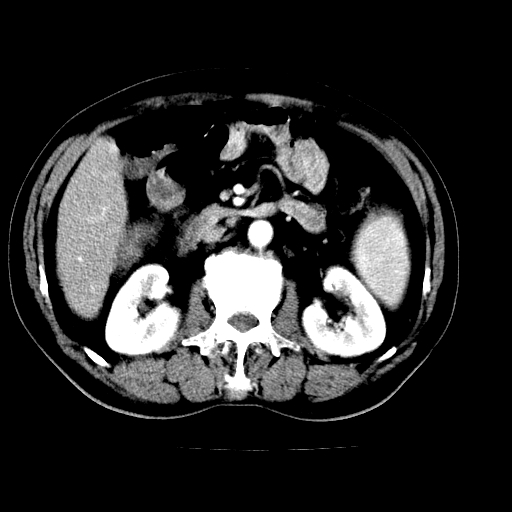

男,66岁,上腹部不适、黄染一周。彩超示:肝左叶占位,肝内胆管扩张,胆总管扩张,胆总管占位?

肝左叶不规则软组织肿块影,边缘不规整邻近肝实质受累分界不清;肝内胆管(左叶)明显扩张成“软藤状”,诊断:肝左叶胆管细胞癌。

肝左叶占位性病变,并胆管扩张,符合胆管细胞癌ct表现,门脉左支受累,左肾囊肿。窗宽太窄了,其他的看不清

左叶胆管细胞癌累及胆总管,门脉左支受侵,慢性胆囊炎胆结石,左肾小囊肿

肝左叶不规则软组织肿块影,边缘不规整邻近肝实质受累分界不清;肝内胆管(左叶)明显扩张成“软藤状”,诊断:肝左叶胆管细胞癌。胆囊钙乳症。